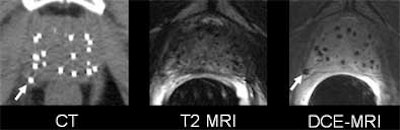

| Wayward brachytherapy seeds are well visualized, and better localized, in the contrast-enhanced MRI (the "D" in DCE-MRI stands for "dynamic," which is not necessary to optimize seed visualization, according to the authors). In patient 1 (top), a brachytherapy seed has migrated to the neurovascular bundle. In patient 2 (below), CE-MRI shows a seed that has lodged in a seminal vesicle, but cannot be localized in CT image at left. In patient 3 (bottom), the migration of seeds to the penile bulb is readily visualized on contrast-enhanced ("CE") MRI, lower right. All images courtesy of Dr. Klaus Kubin. |

According to the results, the T1-weighted GRE sequence localized 92% of the seeds overall (with per-patient accuracy ranging from 87%-99%), 14% of which were periprostatic. Twenty-five percent of the seeds were located in the neurovascular bundle, and 4% in the seminal vesicles.

T2-weighted MRI localized 78% of the seeds overall (range, 74%-86%), including 12% in periprostatic distribution, which was diagnosed more accurately on the T2 images. Twenty-four percent were found in the neurovascular bundle and 3% in the seminal vesicles, Kubin said.

CT won the sensitivity race, locating 97% of the seeds (range, 95%-100%). Two percent were suspected to be extraprostatic; however, the group was unable to assign the seeds to specific periprostatic structures.

The group concluded that T1- and T2-weighted MR were both more accurate for postbrachytherapy seed distribution than CT.

"The main idea is that the prostate takes up contrast media in general, not only the cancer, so if you wait long enough (up to 11 minutes after injecting contrast) the whole prostate is contrast enhanced," Bloch said. "But the seeds, of course, you see as voids because there is no contrast uptake. So if you use high-spatial-resolution MRI, no matter if it’s T2- or T1-weighted contrast enhanced, you see very nicely the prostate, the prostate capsule, and the neurovascular bundle, the penile bulb, and the rectal wall, but until now you couldn’t see the seeds."